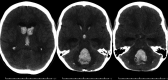

Observations: The authors present the case of a 14-year-old patient 8.2 years after CRT who experienced intracerebral hemorrhage. Autopsy demonstrated minimal pathological change without evidence of vascular malformation or aneurysm. These findings were unexpected given the degree of hemorrhage in this case. However, in the absence of other etiologies, it was believed that late-delayed radiation effect was the cause of this patient's fatal hemorrhage.